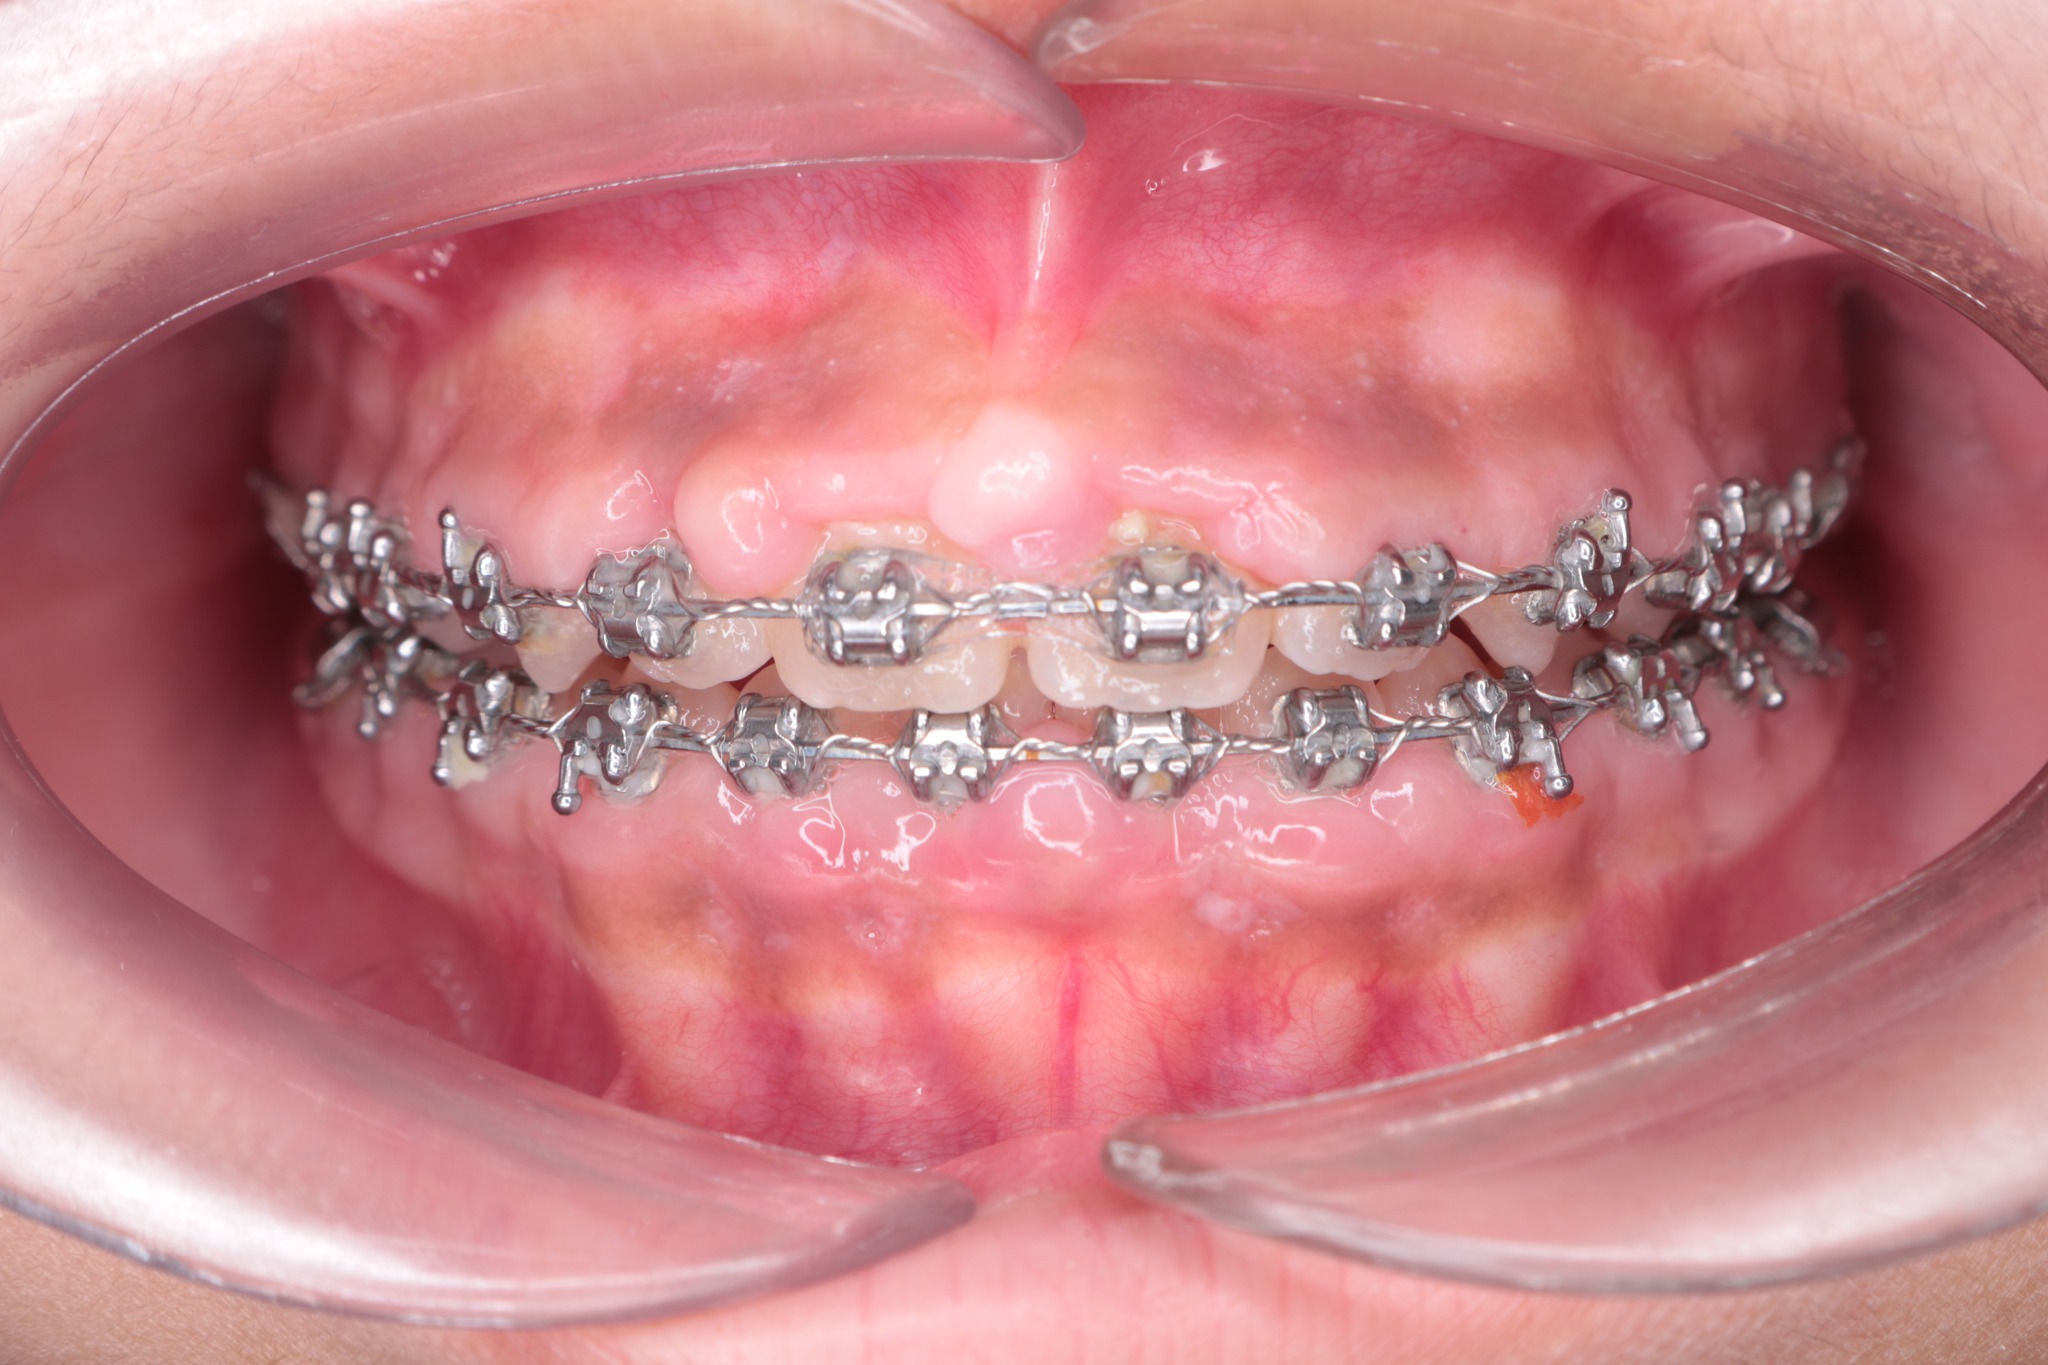

Mắc cài, vùng dưới dây cung và xung quanh đế mắc cài tạo ra các “góc chết”, ít oxy - điều kiện lý tưởng cho vi khuẩn Gram âm phát triển. Những vi khuẩn này giải phóng nội độc tố Lipopolysaccharide (LPS) và các enzyme phân giải protein, kích hoạt phản ứng viêm mạnh mẽ trong dịch rãnh lợi. Do đó, khách hàng niềng răng cần tuân thủ tuyệt đối các chỉ định của bác sĩ về việc vệ sinh răng miệng tại nhà để loại bỏ hoàn toàn mảng bám, giảm hình thành cao răng.

Khách hàng viêm lợi do không vệ sinh đúng cách

Bản thân lực siết răng cũng gây ra một phản ứng viêm vô khuẩn có kiểm soát để tiêu xương và bồi xương. Nếu kết hợp với độc tố từ vi khuẩn mảng bám, phản ứng này sẽ chuyển sang nhiễm khuẩn cấp tính hoặc mãn tính. Viêm lợi, viêm nha chu chính là nguyên nhân chủ yếu gây tiêu xương, tụt lợi và làm giảm tuổi thọ của răng.

Tại Lạc Việt Intech, khách hàng được làm sạch cao răng và vệ sinh răng miệng mỗi lần tái khám. Nếu bị viêm lợi, khách hàng sẽ được bác sĩ điều trị và hướng dẫn chăm sóc tại nhà để bệnh không tiến triển thành viêm nha chu.